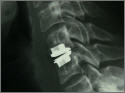

Halswirbelsäule

Die neue OP-Methode in Bildern

Schonende OP-Methode: Als neueste Operationsmethode an der Halswirbelsäule steht uns nun mehr als Ersatz einer abgenützten Bandscheibe die künstliche Bandscheibenprothese zur Verfügung. Sie erhält die Beweglichkeit der Halswirbelsäule auch nach der Operation.